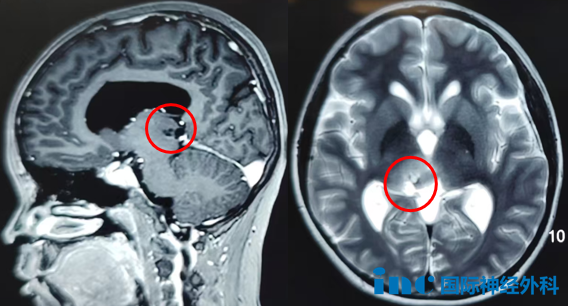

案例3:20岁女性丘脑海绵状血管瘤

术前症状:视野受限,焦点外视觉模糊,伴头痛症状

手术风险:丘脑海绵状血管瘤临床罕见,出血后常引起偏瘫等神经功能障碍,治疗极其棘手。形象比喻而言,丘脑功能类似插头转换器,若缺失此转换器,无法将信息输送至大脑。故丘脑损伤可能导致患者成为"木头人",即对外界刺激缺乏反应。对法学专业的小雨而言,此诊断犹如晴天霹雳。

术后情况:病灶完全切除,术后第一天巴教授查房时,患者恢复良好,可在病床自主活动手足。"太好了!她还是原来的她,用她自己的话说——我没有变笨,没有偏瘫,没有面瘫……"母亲激动地分享。术后3个月,患者重返校园,以全科通过的优异成绩实现完美回归。